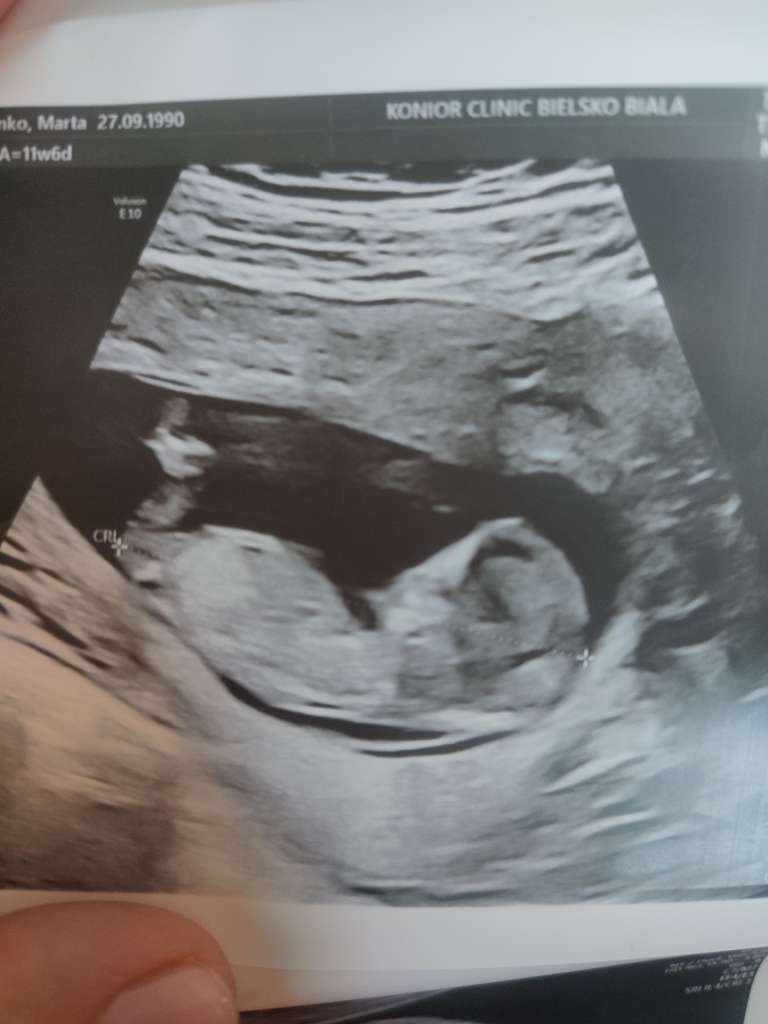

wg dzisiejszego USG 11+5. Ja też się stresowałam strasznie i maluch chyba to czuł- nie wiem czy to już możliwe i dość mocno szalał na początku ale im byłam spokojniejsza po kolejnych pomiarach tym bardziej dziecko się uspokajało.

ja również dzisiaj 11+5 wg ostatniego USG 😊 myślę, że na pewno współodczuwał z Tobą, stąd te ruchy. Swoją drogą to musi być niesamowite zobaczyć jak takie maleństwo szaleje w brzuszku, a póki co się tego nie odczuwa. Dla mnie ostatnie usg było takie odrealnione w stylu „serio, mam takiego malucha w sobie?”. 🤣 Pewnie tak przeżywam ze względu, że to jednak pierwsza ciąża.

Dla Części z was to już nie pierwsza ciąża więc może jesteście w stanie podpowiedzieć czy u was takie zdjęcie wskazywało na którąś płeć? Wrzucam przekrój i nocnikowe.

Miałyście podobnie? Z przekroju wydawało mu się że dziewczyna z nocnika chłopak 🤦 czytam że na tym etapie raczej się ocenia po wyrostku i przekroju.